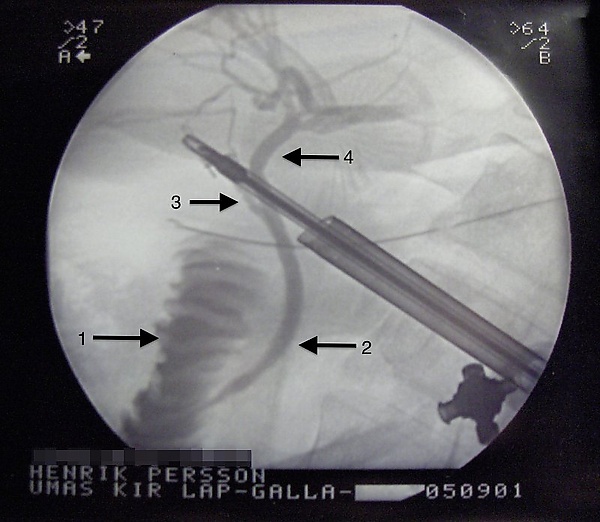

Лапароскопическая хирургия

Операция выполняется под наркозом. Лапароскопическая холецистэктомия производится через проколы брюшной стенки. Наиболее часто применяемая техника операции предусматривает выполнение четырёх проколов, два из которых имеют длину по 5 миллиметров, другие два — по 10 миллиметров. В брюшную полость вводятся хирургические инструменты, а также лапароскоп — специальный прибор, выводящий на монитор объемное изображение внутренних органов. Также существует однопортовая холецистэктомия по технологии SILS и NOTES.[1]